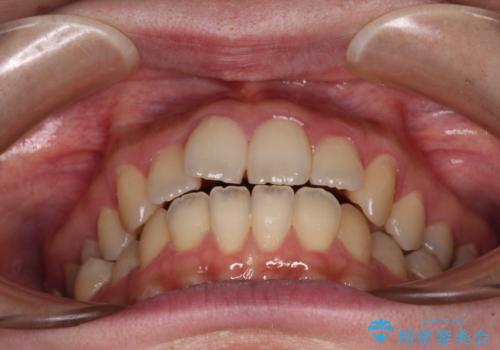

- 捻れた前歯が飛び出しており、口が閉じにくいとのことで来院された患者様です。

出っ歯というわけではないものの、前歯の捻転により口唇が押し出されている状態でした。

親知らずを抜去し、歯列全体を後方に移動させつつ、IPR(歯と歯の間を削る)でスペースを獲得し、インビザラインを用いて叢生を解消しながら前歯の突出を改善することとしました。

インビザラインは、患者様の協力無しには成立しない治療ですが、しっかりと装着時間を遵守してくださり、1年弱で治療を終えることができました。